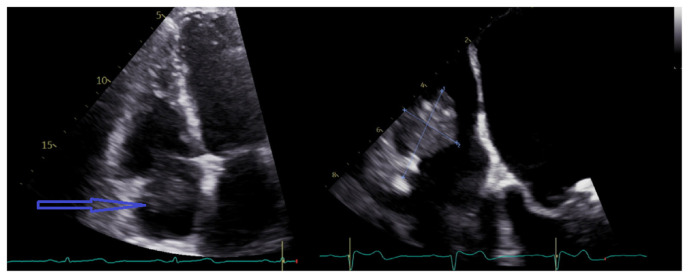

Intradialytic Atrial Fibrillation With Rapid Ventricular Response From Catheter-related Right Atrial Thrombus.

Right atrial thrombus is a rare complication of hemodialysis catheter with an incidence of <6 %. New-onset atrial fibrillation can be the first symptom of catheter-related right atrial thrombus (CRAT) in a patient with long-term dialysis catheter. Therefore, evaluation for CRAT is justified in such scenario. We highlight a case report where a new-onset atrial fibrillation led to the discovery of a right atrial thrombus in a patient with long-term dialysis catheter.